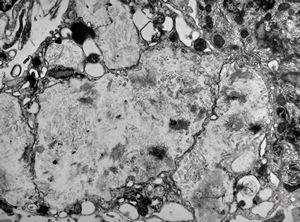

M,54y. | Whipple disease

Whipple disease